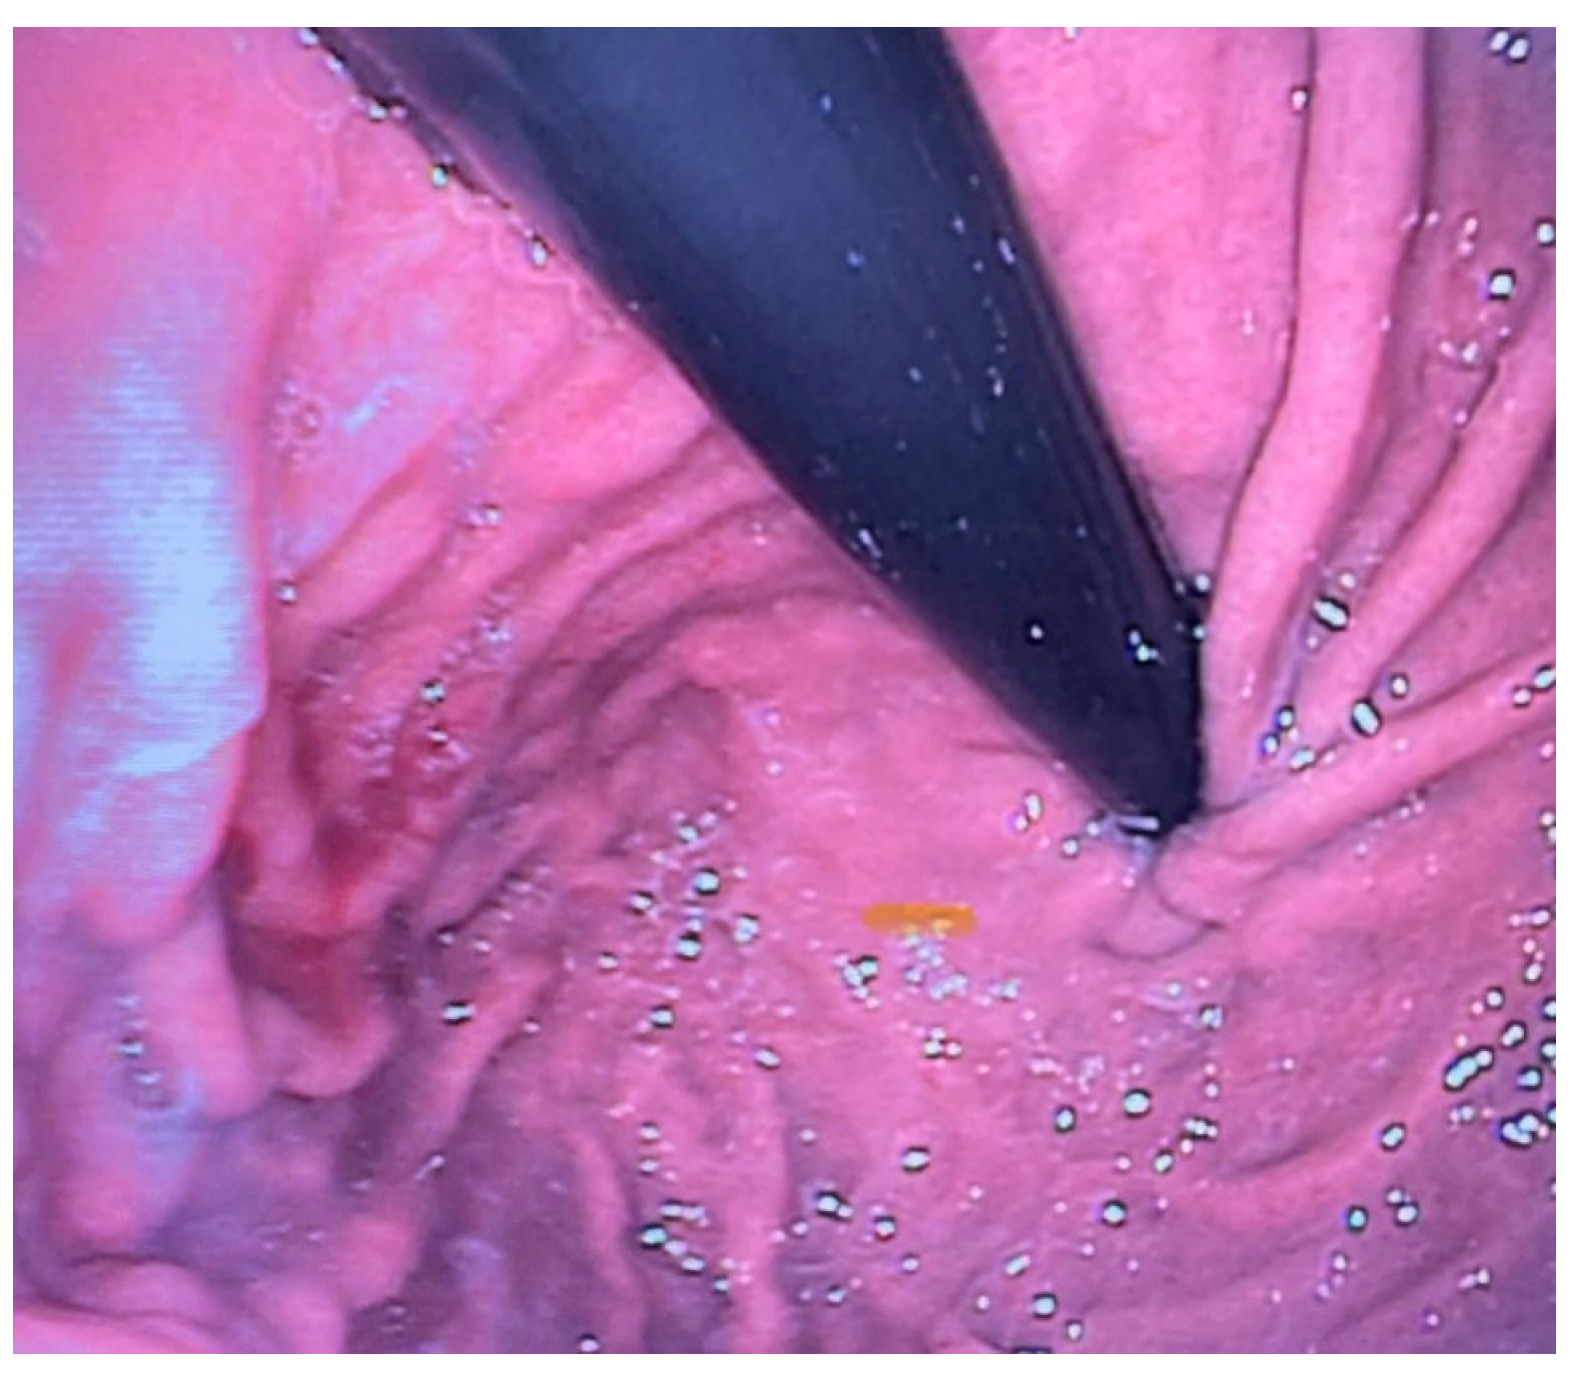

Esophagogastroscopy allowed us to obtain multiple pieces of information in our patients: it allowed us to assess both esophageal and gastric anatomy under direct vision, as well as the contractility of the lower esophageal sphincter. It also provided insights into the macroscopic characteristics of the esophageal and gastric mucosa (Figure 2 and Figure 3). Moreover, by performing at least four esophageal biopsies during each procedure, we were able to confirm the presence of esophagitis and classify its type, which could be a potential consequence of gastroesophageal reflux disease (GERD), using histopathological analysis [9].

Gastroesophageal reflux (GER) is defined as the backflow of stomach contents into the esophagus, with or without regurgitation or vomiting. It is considered pathological when it leads to bothersome symptoms or complications such as stenosis, pulmonary consequences, or esophagitis (Figure 4) [10].

Figure 2. Site of the previous esophageal anastomosis with mild caliber reduction and without evidence of stenosis. Good distensibility on insufflation and smooth instrument passage. Mild caliber discrepancy between the upper and lower stumps.